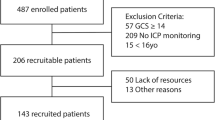

The need for approval by the institutional review board was waived for this study since it only made use of retrospective anonymized data. The Declaration of Helsinki and the Strengthening the Reporting of Observational Studies in Epidemiology (STROBE) guidelines were adhered to throughout its completion [22]. All data were obtained from the American College of Surgeons Trauma Quality Improvement Program (TQIP) database, a national multi-institutional database of all trauma patients collected from more than 850 participating trauma centers across the United States. This database is gathered for risk-adjusted benchmarking and quality improvement. Furthermore, well-trained data registrars amass more than 100 patient-related and center-related variables. The TQIP plays a central role in the development of evidence-based interventions to enhance patient quality of care by looking at the enrolled centers’ performances [23]. These included patient age, sex, race, initial Glasgow Coma Scale (GCS) in the emergency room (ER), intracranial injuries, abbreviated injury scale (AIS) for each region, surgical interventions, comorbidities, length of stay and in-hospital mortality. All adult patients (18 years or older) registered in the TQIP database between 2013 and 2017 who suffered an isolated severe traumatic brain injury (sTBI) were considered for inclusion. An isolated sTBI was defined as a head AIS ≥ 3 with an AIS ≤ 1 in all other regions. Patients were excluded if they had a head AIS of 6 since these injuries are generally considered non-survivable.